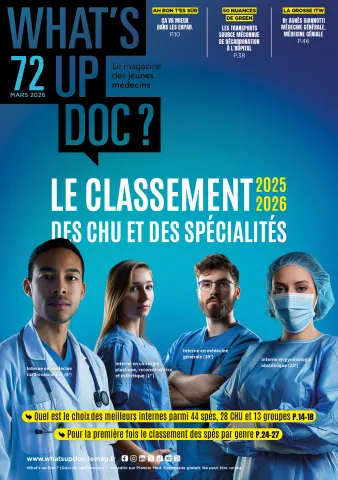

what's up doc - publié par AP